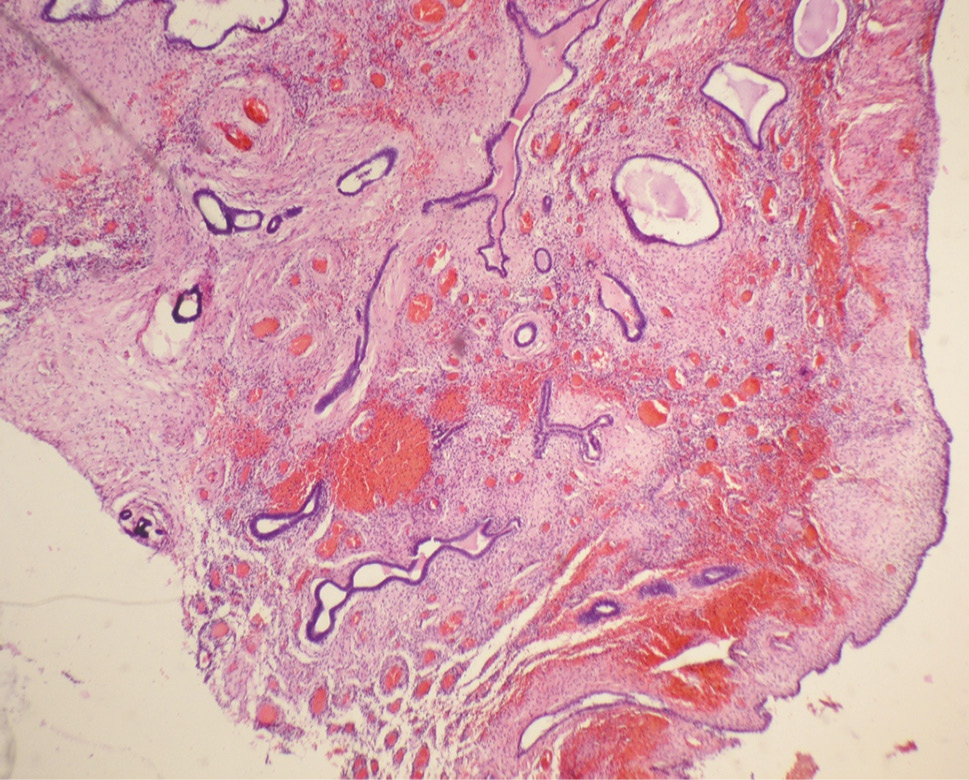

- During a hysteroscopic examination, endometrial polyps were visualized in 43.3% of cases. The main complaint was abnormal uterine hemorrhage. Oval pale pink formations with a smooth surface and slight vascularization on the pedicle were determined hysteroscopically. Large endometrial polyps (1.5–2.0 cm) were detected in 20.7% of cases, medium polyps (1.0 cm) were found in 78.5% of cases. In patients of this age group, glandular-fibrous and fibrous polyps prevailed (62.8%) in the shape of formations on the pedicle with cystic-dilated glands (Fig. 4).

Fig. 4. Glandular fibrous endometrial polyp of the senile type with cystic expansion of the glands and severe circulatory disorder (hematoxylin and eosin staining at ×40 magnification)

Рис. 4. Железисто-фиброзный полип эндометрия «сенильного типа» с кистозно расширенными железами и выраженным расстройством кровообращения (окраска гематоксилином и эозином, увеличение ×40)